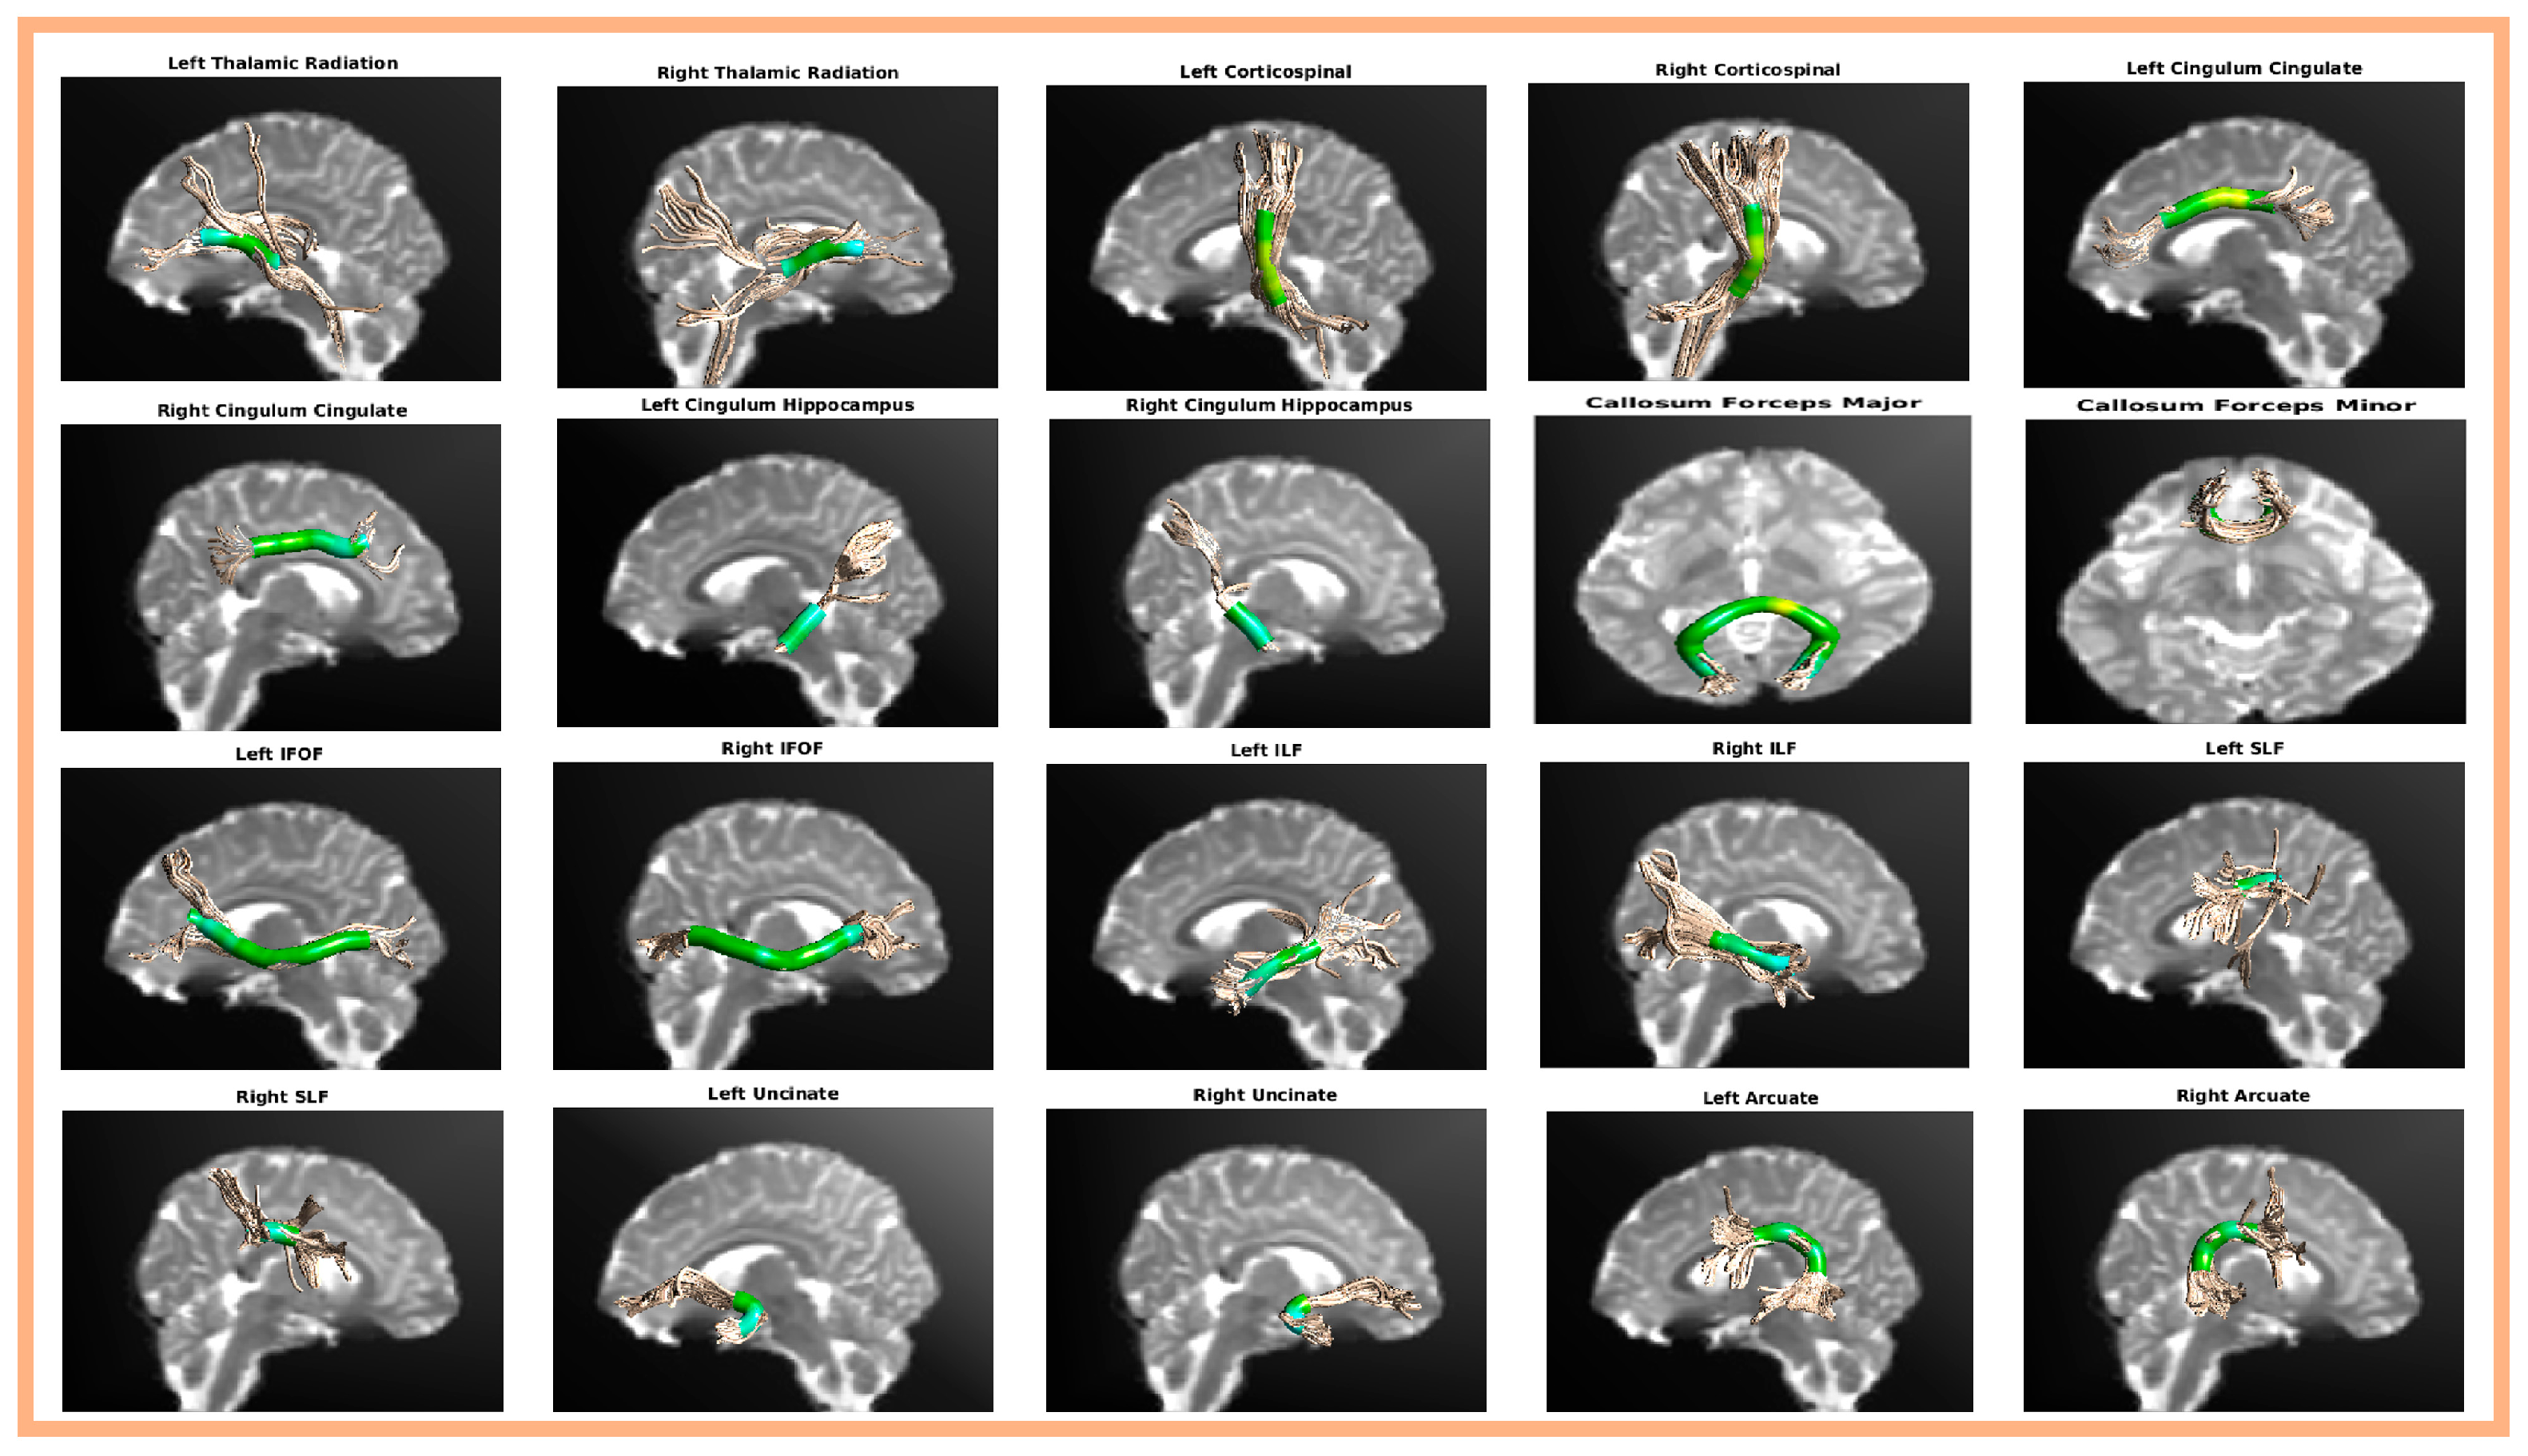

2.3. Automatic Fiber Tract Quantification (AFQ) Analysis